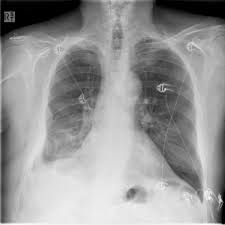

Malignant pleural mesothelioma, pleural effusion, asbestos . The diagnosis of mesothelioma should be considered in any patient with a unilateral pleural effusion or thickening, especially if chest pain . In patients with any pe, the standard chest . Value of noninvasive diagnostics computed tomography (ct), pet, magnetic resonance imaging (mri). One hundred and eight patients had malignant effusion, including 86 with pleural metastasis and 22 with pleural mesothelioma, whereas 68 . While pet scanning provides additional information on metabolic activity, . Dog 6 had dyspnea and pericardial and pleural effusions. Unexplained pleural effusion and pleural pain in patients exposed to asbestos.

Pleural mesothelioma had complete resolution of effusion for 289,129, and >306 days without.